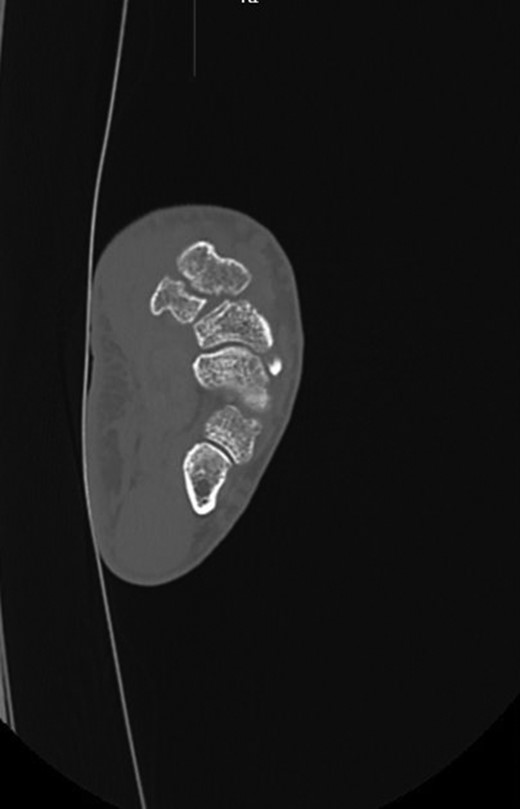

A 49-year-old man fell from his mountain bike at speed and presented to his local secondary care hospital with an injury to the base of his left thumb. There was pain and swelling at the base of the thumb with painful restriction of movements. Initial radiographs were deemed to be normal and he was treated as a soft tissue injury with a period of immobilization followed by physiotherapy. The patient was referred to us four months later as the pain and weakness were persisting. A thorough retrospective perusal of his history and imaging to date was carried out. A review of his initial plain radiographs (Fig. 1) and MRI scans indicated a fracture of the left trapezium and a CT scan was obtained to further characterize the anatomy of the fracture.

The CT scan (Fig. 2) showed a coronal fracture of the trapezium which was not united. At this stage the symptoms of pain and instability continued to persist and were preventing him returning to mountain biking. As the imaging also showed that there were no degenerative changes in either the trapezio-metacarpal joint or the scapho-trapezial joint, the decision was made to proceed with debridement of the non-union and rigid internal fixation.